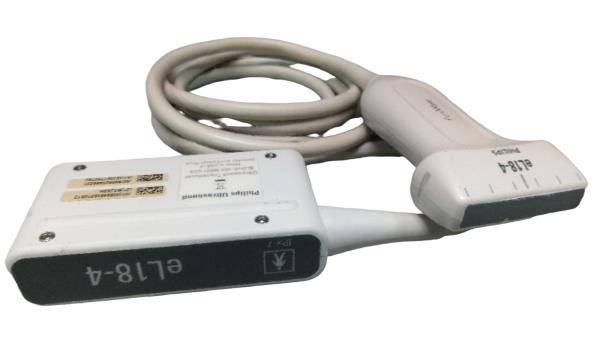

Probe Function: 3.5MHZ convex, abdominal organs

The Diagnostic Ultrasound Scanner is an advanced medical device that uses high-frequency sound waves to create precise images of the body's internal structures. This technology plays an important role in diagnostics because it helps healthcare professionals identify issues such as abnormalities in organs and tissues, leading to early intervention. The incorporation of a Convex and Transvaginal Probe offers versatility, making it suitable for various examinations. Using this ultrasound scanner, doctors can provide better care and ensure patient satisfaction.